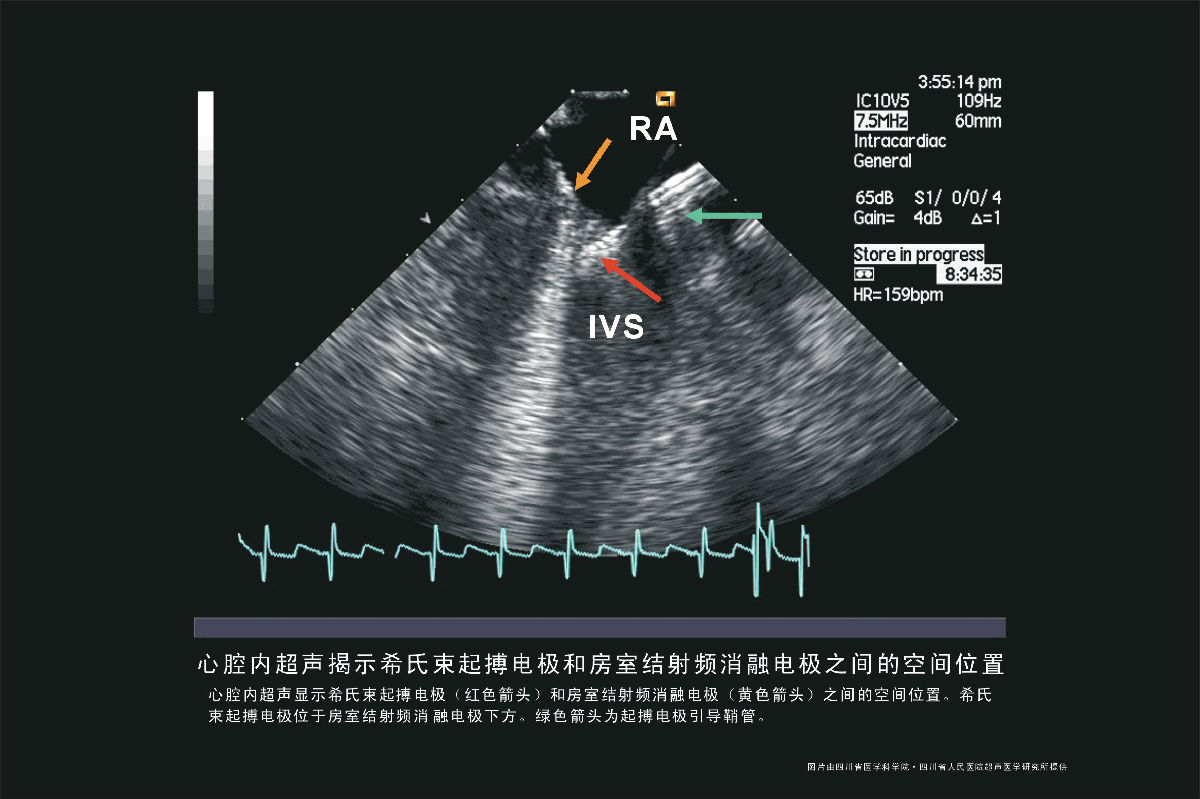

电极空间位置